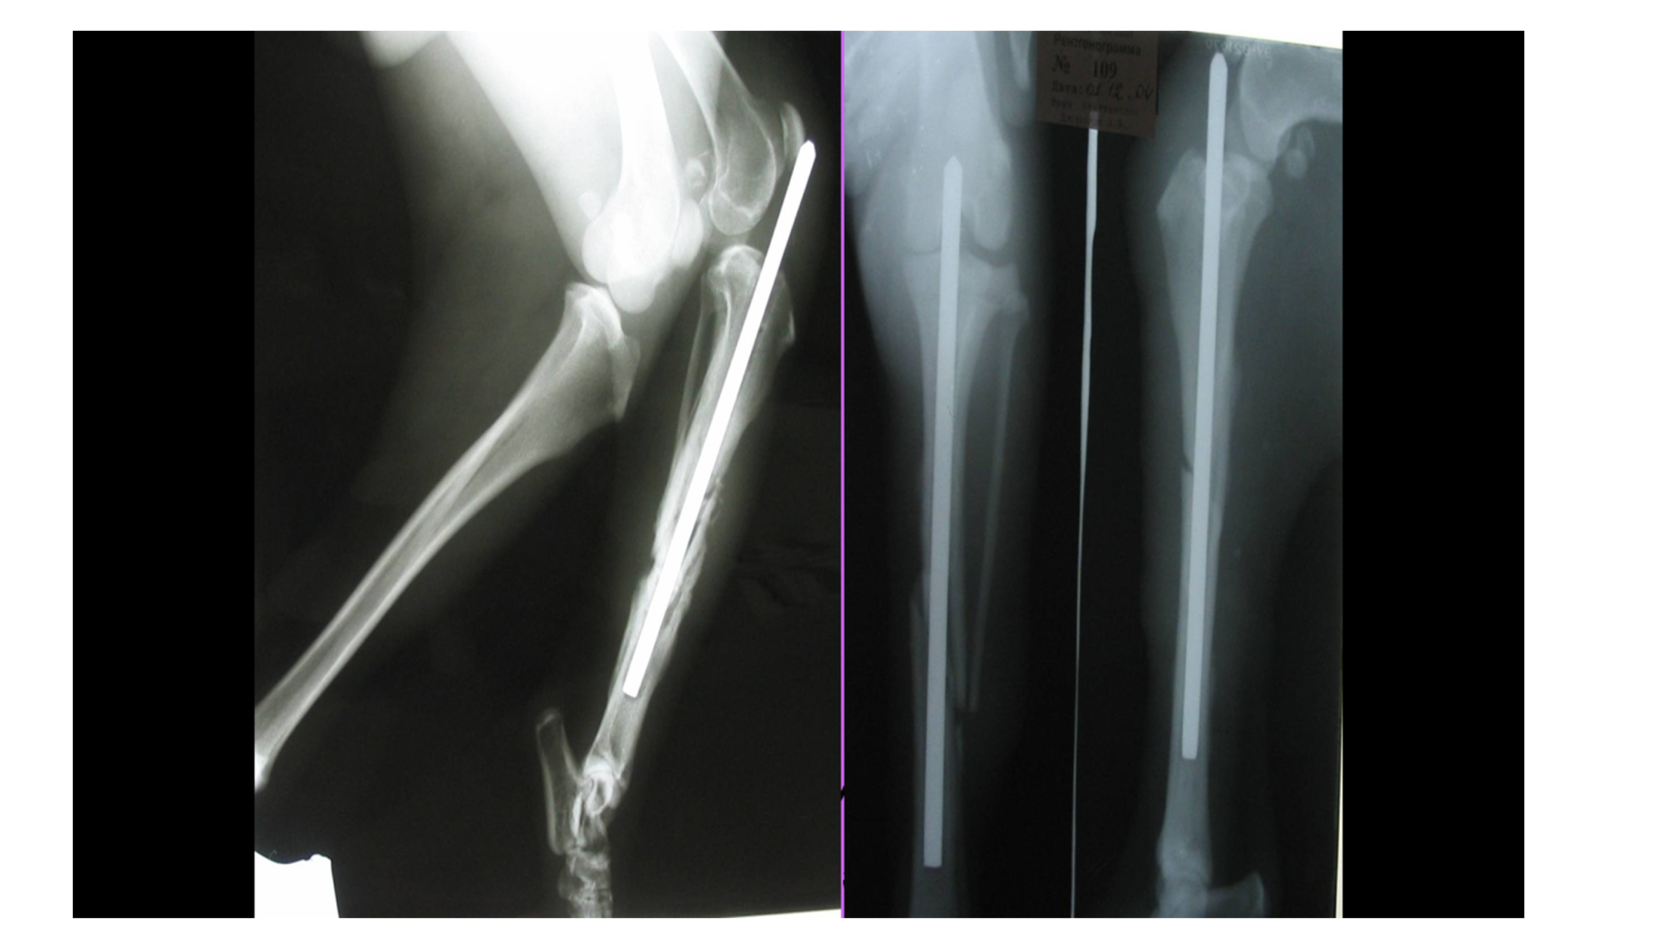

Остеосинтез: частые ошибки

Разберем основы остеосинтеза, преимущества и недостатки методов фиксации, первичные и вторичные методы фиксации и многое другое!

Основы остеосинтеза

Преимущества и недостатки методов